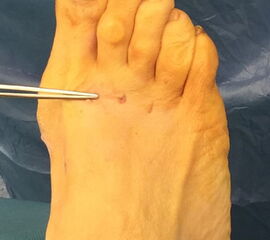

Das hier vorgestellte Konzept beruht auf den grundsätzlichen Überlegungen von Sharma, unter Anwendung der Prinzipien der minimalinvasiven Fußchirurgie. Die Korrektur der Adduktionsfehlstellung der Metatarsalia II bis IV erfolgt über eine modifizierte, lateralisierende, distale, minimalinvasive Metatarsale-Osteotomie (DMMO) (interner Link: OP Technik DMMO). Die Osteotomie der Metatarsalia II bis IV ohne Osteosynthese erlaubt eine limitierte Verlagerung der Metatarsaleköpfchen nach kranial, was ein etabliertes Verfahren zur Therapie einer Metatarsalgie darstellt 7. Eine zusätzliche, im Normalfall unerwünschte Lateralverschiebung der Metatarsaleköpfchen kann bei einem Pes adductus zur Korrektur genutzt werden. Verglichen zu offenen Therapieverfahren ermöglicht dieses Konzept die Korrektur der Adduktionsstellung der Metatarsalia II bis IV bei minimiertem Weichteiltrauma und verkürzter die OP-Dauer. Persönliche Erfahrungen mit dem Verfahren deuten darüber hinaus auf ein geringeres postoperatives Schmerzniveau, eine einfachere Mobilisierbarkeit und eine hohe kosmetische Zufriedenheit hin.

Das hier vorgestellte Verfahren umfasst die Kombination verschiedener etablierter Konzepte, die sich zur Korrektur eines des Pes adductus mit Hallux valgus Deformität in besonderer Weise eignen. Dabei wird eine offene Lapidus Arthrodese mittels winkelstabiler plantarer Platte mit verschiedenen perkutanen distalen Eingriffen zur Korrektur der Pes adductus Fehlstellung kombiniert 8910.

Zum Lesen der Bildbeschreibung und zur Vollansicht bitte die Bilder anklicken.